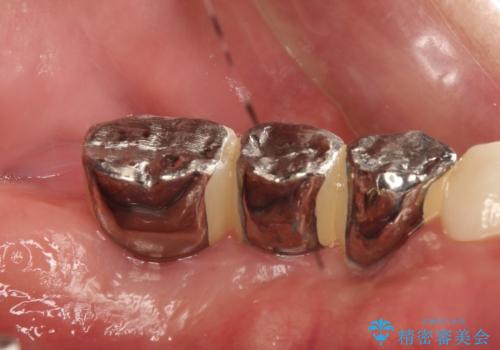

かみ合わせの力が非常に強く、夜間の歯ぎしり・食いしばりもひどかったため、奥歯はメタルオクルーザルの設計でかぶせ物を製作しています。

かぶせ物の種類:PFZ / PFM metal occlusal